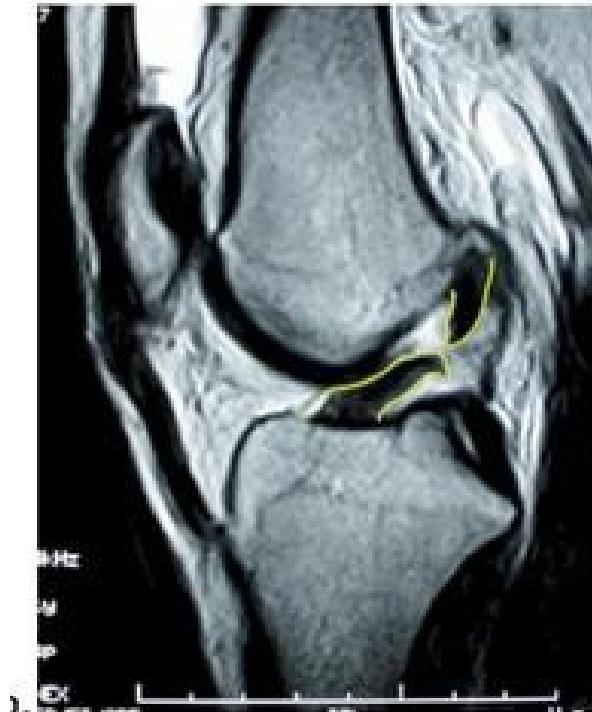

Question: What is your finding? ACL tear

Imaging

Question: What is your finding?